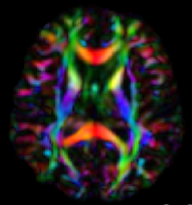

Inverse Problems in Neuroscience: Susceptibility Tensor Imaging

6 times faster